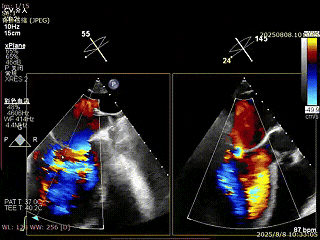

XPLAN切面2区偏3区中重度反流

3D enface 切面

3D enface观察反流